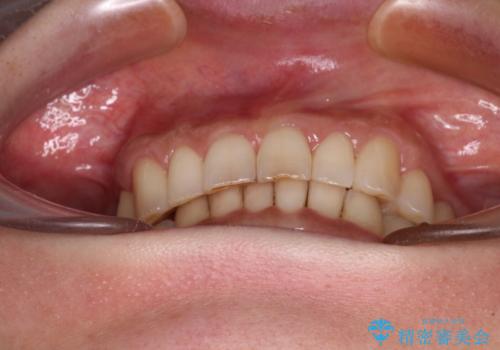

デコボコの歯とむし歯 インビザライン矯正治療とむし歯治療

その後、オールセラミッククラウンにて補綴治療を行う予定でしたが、処置した歯以外にも治療が必要と思われる歯があったり、デコボコした歯列も気になるとのことで、患者様希望によりインビザラインにてマウスピース矯正を行うこととしました。

まずは矯正治療前に必要なむし歯処置を行い、その後矯正治療を行ってから、最後にオールセラミッククラウンなどで補綴治療を行うこととしました。

咬合力が非常に強く、全体的に歯が擦り減っている状態であったので、理想的な咬み合わせを達成することは難しく、また咬合力が強い方のマウスピース矯正は、思い通りに動かないことがあるため、ワイヤー矯正の方が望ましいように思えました。

治療途中で2年強、体調を崩されて通院ができなくなってしまったため、必ず通院が必要なワイヤー矯正ではなく、マウスピース矯正で結果的には無事に治療を終えることができました。